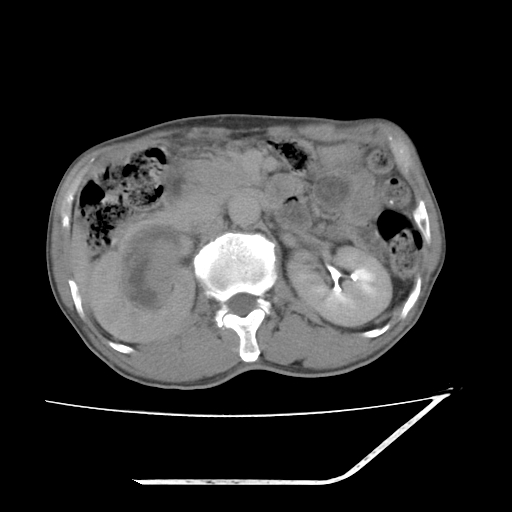

平扫

增强

考虑右肾盂癌,肾动脉受侵,右肾功能减退,右肾盂输尿管积水,管壁增厚,考虑种植转移,应该把下面扫完的

支持右侧肾盂癌伴肾静脉瘤栓形成可能性大,右肾结石.肝右叶后段低密度影,不除外转移.

右肾囊实性占位,支持肾癌,窗宽窗位不是很理想

右肾盂旁ca并肾静脉瘤栓形成/肾功能降低。

右肾结石。

右肾盂癌,肾动脉受侵,右肾盂输尿管积水,管壁增厚,考虑种植转移

支持 右侧肾盂癌伴肾静脉瘤栓形成可能性大,右肾结石;肝右叶后段低密度影,不除外转移。

1.右侧肾盂癌伴肾盂积水。

2.肾脏功能减退,原因有:(1)肾动脉受侵。(2)肾静脉受侵(3)肾积水,等。本例,肾动脉显影较好,但受压明显;肾静脉无明显显示,受压或静脉癌栓,下腔静脉腔内未见明显充盈缺损。

3.右侧上段输尿管扩张,原因:(1)积水所致;(2)种植。